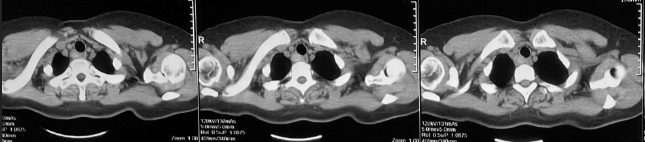

2015年因夜间突发憋气,查CT(图2):可见气管右后方囊泡状改变,与气管相通。患者未予诊治。

图2 胸部CT(2015年):气管后方可见囊样结构(箭头所指)

2016-7常规复查(图3):气管右后方见一高密度影及囊腔样改变。

图3 胸部CT(2016年7月):气管右后方见一高密度影及囊腔样改变